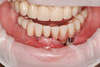

2- Les implants dans le cas d'une situation de déchaussement dentaire

Dans ce cas, un traitement anti infectieux a permis de traiter la maladie de gencive et de conserver les dents du bas mais pas les dents du haut.

La mise en place de plusieurs implants et d'une prothèse transvissée à permis de remplacer toutes les dents de la mâchoire supérieure